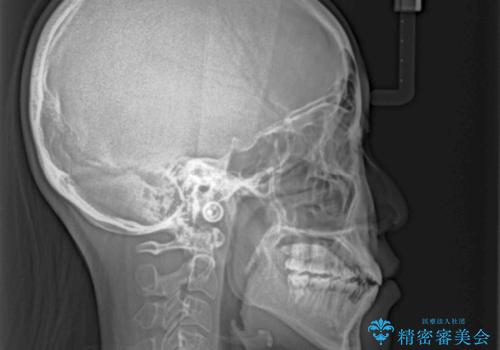

八重歯とオープンバイト 急速拡大装置を用いた矯正治療

急速拡大装置で上顎骨を十分に拡大できたことで、非抜歯で八重歯を歯列に納めることができました。

患者様はもちろん、我々もここまで綺麗に仕上げられるとは想像もできず、お互いに大変満足な治療となりました。